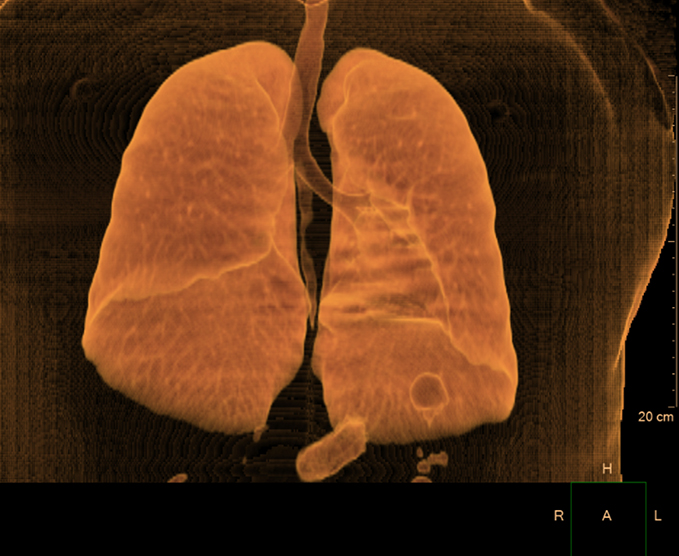

- Tórax (Simple y contrastada)

- Arterias pulmonales